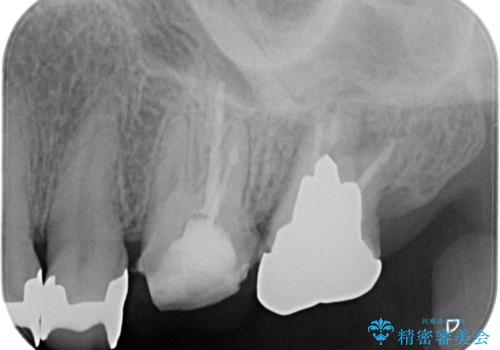

【再根管治療】オールセラミッククラウンによる修復

- 治療途中の歯があることを主訴に来院されました。

根管治療を行なったのちオールセラミックにて修復治療を行なっております。

第二大臼歯の治療は希望されませんでした。